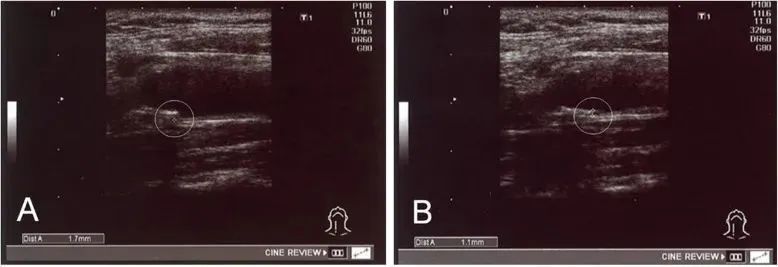

在《Stem Cell Res Ther》发表的一篇文章中,研究者收集了78名使用自体干细胞治疗动脉硬化的患者数据,包括他们给药前后的脂质分布、内膜中膜厚度 (IMT)等。

②、18例IMT值异常(≥1.1 mm)的患者,在治疗后IMT值均显著减少;

经过治疗,实验中一名患者 IMT 从 1.7 毫米降至 1.1 毫米